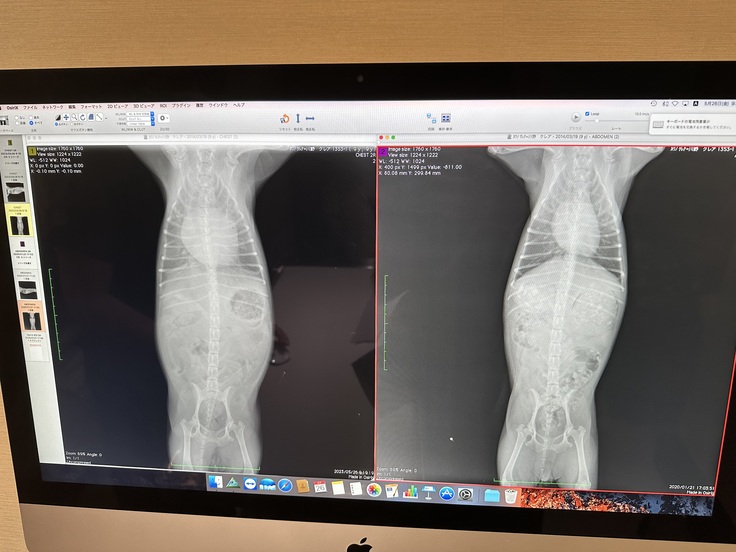

写真は病気が分かった今年5月の時の心臓(左側)とその3年前(右側)のクレアの心臓の写真です😣11月には手術予定の病院でこれよりさらに大きくなっていると言われました。